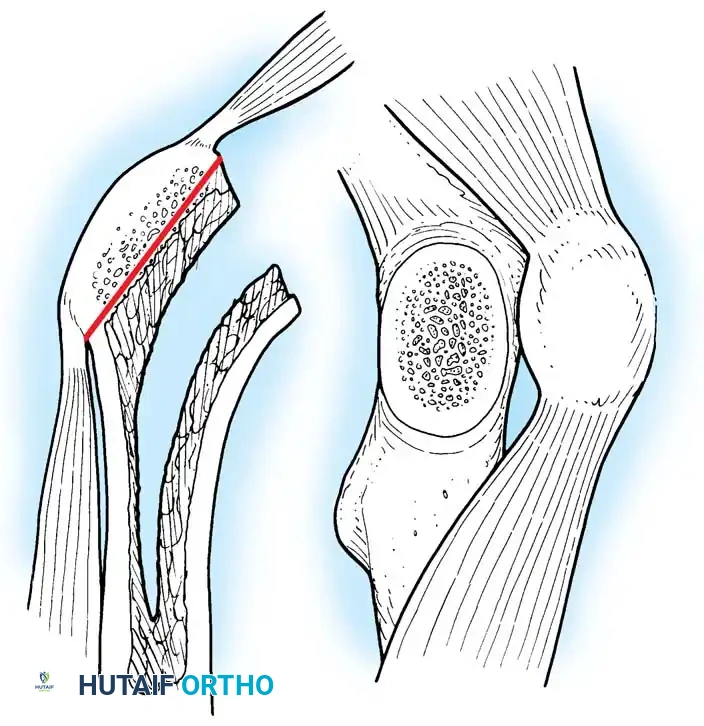

🔪 Surgical Technique: Femoral Neck Osteotomy

Using the preoperative template as a guide, measure the distance from the lesser trochanter to the planned resection level. Use a reciprocating or oscillating saw to resect the femoral neck at the appropriate angle (usually 45 degrees).

Image